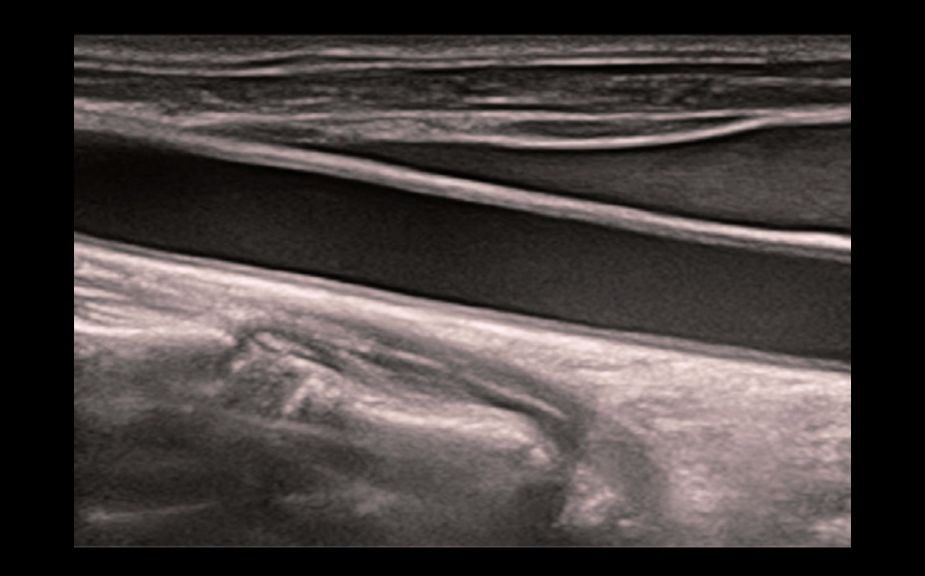

–ė–Ĺ–Ĺ–ĺ–≤–į—Ü–ł–ĺ–Ĺ–Ĺ–į—Ź –ĺ—Ü–Ķ–Ĺ–ļ–į –∂–Ķ—Ā—ā–ļ–ĺ—Ā—ā–ł: HiFR STE

–í 10 —Ä–į–∑ –Ī–ĺ–Ľ–Ķ–Ķ –≤—č—Ā–ĺ–ļ–į—Ź —á–į—Ā—ā–ĺ—ā–į –ļ–į–ī—Ä–ĺ–≤ –Ņ—Ä–ł —Ä–į–Ī–ĺ—ā–Ķ —Ä–Ķ–∂–ł–ľ–į STE

–í—č—Ā–ĺ–ļ–į—Ź —á—É–≤—Ā—ā–≤–ł—ā–Ķ–Ľ—Ć–Ĺ–ĺ—Ā—ā—Ć –ļ –ī–≤–ł–∂–Ķ–Ĺ–ł—é –ī–Ľ—Ź –Ņ–ĺ–≤—č—ą–Ķ–Ĺ–ł—Ź —Ā—ā–į–Ī–ł–Ľ—Ć–Ĺ–ĺ—Ā—ā–ł –ł —ā–ĺ—á–Ĺ–ĺ—Ā—ā–ł

HiFR STE –Ĺ–ĺ–≤–ĺ–ĺ–Ī—Ä–į–∑–ĺ–≤–į–Ĺ–ł—Ź –ľ–ĺ–Ľ–ĺ—á–Ĺ–ĺ–Ļ –∂–Ķ–Ľ–Ķ–∑—č

HiFR STE –Ņ–Ķ—á–Ķ–Ĺ–ł

–ė–Ĺ–Ĺ–ĺ–≤–į—Ü–ł–ĺ–Ĺ–Ĺ–į—Ź –ĺ—Ü–Ķ–Ĺ–ļ–į –∂–Ķ—Ā—ā–ļ–ĺ—Ā—ā–ł: HiFR STE

–í 10 —Ä–į–∑ –Ī–ĺ–Ľ–Ķ–Ķ –≤—č—Ā–ĺ–ļ–į—Ź —á–į—Ā—ā–ĺ—ā–į –ļ–į–ī—Ä–ĺ–≤ –Ņ—Ä–ł —Ä–į–Ī–ĺ—ā–Ķ —Ä–Ķ–∂–ł–ľ–į STE

–í—č—Ā–ĺ–ļ–į—Ź —á—É–≤—Ā—ā–≤–ł—ā–Ķ–Ľ—Ć–Ĺ–ĺ—Ā—ā—Ć –ļ –ī–≤–ł–∂–Ķ–Ĺ–ł—é –ī–Ľ—Ź –Ņ–ĺ–≤—č—ą–Ķ–Ĺ–ł—Ź —Ā—ā–į–Ī–ł–Ľ—Ć–Ĺ–ĺ—Ā—ā–ł –ł —ā–ĺ—á–Ĺ–ĺ—Ā—ā–ł

HiFR STE –Ĺ–ĺ–≤–ĺ–ĺ–Ī—Ä–į–∑–ĺ–≤–į–Ĺ–ł—Ź –ľ–ĺ–Ľ–ĺ—á–Ĺ–ĺ–Ļ –∂–Ķ–Ľ–Ķ–∑—č

HiFR STE –Ņ–Ķ—á–Ķ–Ĺ–ł